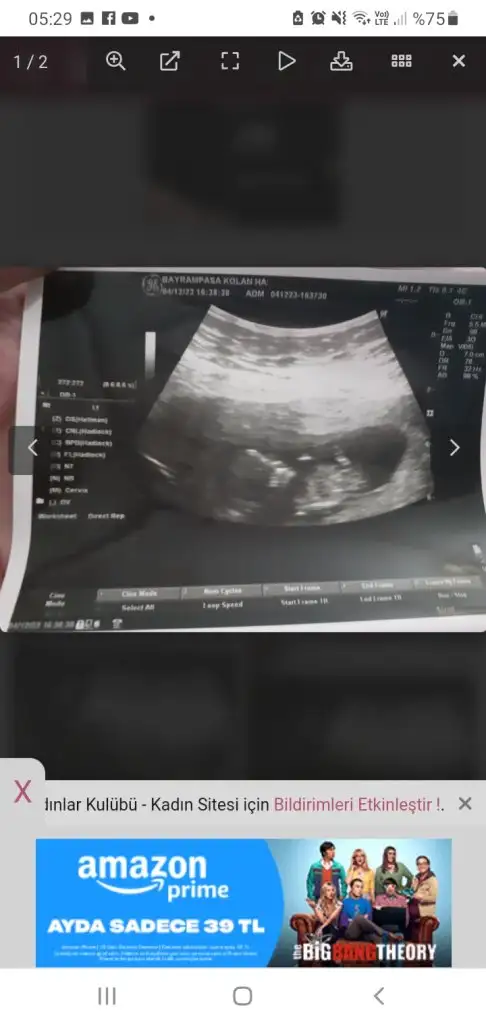

• Screenshot_20231206-052921_Chrome.webp

Screenshot_20231206-052921_Chrome.webp

20,9 KB · Görüntüleme: 273